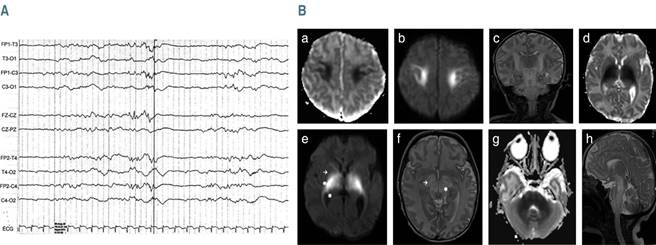

En el electroencefalograma (EEG) se observó actividad anormal, paroxística a nivel frontal y temporal, así como epileptiforme bilateral en foco bitemporal (Figura 2A). Se inició tratamiento con fenobarbital a 3 mg/kg/día, con mejoría de las convulsiones, pero con tendencia al sueño.

Figura 2: A) Electroencefalograma que muestra ráfagas de ondas bajas de aspecto agudo con predominio bitemporal y actividad epileptiforme interictal en el foco bitemporal. B) Resonancia magnética: disminución de la señal en la secuencia potenciada en T1 y aumento en T2. a y b) Afectación del tracto corticoespinal y restricción de la secuencia de difusión en la sustancia blanca perirrolándica. c) Secuencia coronal T2. d y e) Globo pálido [→], brazo posterior de la cápsula interna [ ] y tálamo [☼]. f) Pedúnculos cerebrales [→] y núcleos rojos [☼]. g) Restricción de la difusión en los pedúnculos cerebelosos. h) Corte lateral.

La resonancia magnética nuclear (RMN) del encéfalo mostró una restricción bilateral y simétrica en la secuencia de difusión, con disminución de la señal en T1 y aumento en T2, con afectación del tracto corticoespinal (Figura 2B).